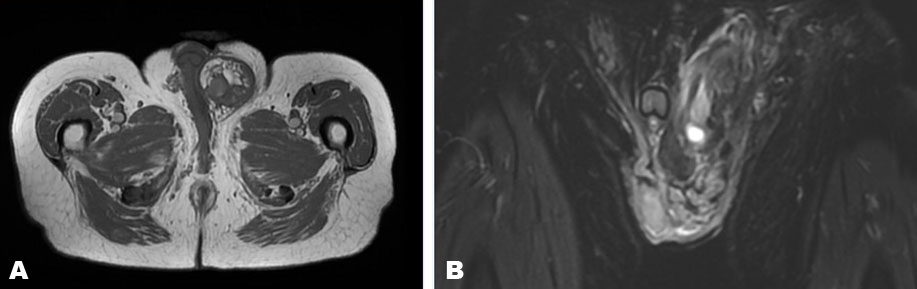

The patient was then referred to our institution. A CT scan of the chest, abdomen, and pelvis showed a mass with no metastatic disease, but it did reveal that the tumor was encroaching on the left testicle with some displacement of the penis (Figure 4). Magnetic resonance imaging (MRI) of the pelvis was performed revealing a large, solid heterogenous soft tissue mass containing macroscopic fat centered in the left inguinal canal with marked thickening of the external spermatic fascia (Figure 5). The imaging appearance was compatible with his given history of sarcoma. It also showed a small, peripherally enhancing fluid collection measuring up to 4 cm in subcutaneous fat superficial to the mass in the left inguinal canal which was thought to be a seroma or abscess related to the biopsy.

Figure 5: (A) Axial T1-weighted unenhanced MR imaging through the left inguinal canal demonstrates marked thickening of the external spermatic fascia with an internal irregular, lobular, hemorrhagic mass displacing hypertrophic fat with edematous or infiltrative septal thickening. (B) Coronal STIR-weighted MR imagining through the same mass demonstrated the mixed signal heterogenous mass with secondary venous congestion and robust edema throughout the left scrotum and inguinal canal.